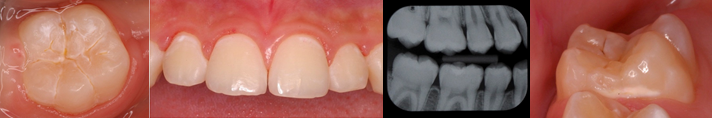

初期う蝕のマネジメントには、う蝕を早期に発見(Detection)して、診断結果を患者さんと共有することが大事です。初期う蝕の診査診断には、ICDASとXRが必要です。

今回のセミナーでは、ICDASとXRを解説した後に、クイズを行って理解を深めます。受講後には、臨床で使えるようになることをセミナーの目的としています。